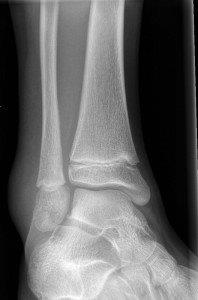

Toddler's fracture

Toddler's fractures

• Follow up Orthopaedic Fracture Clinic in 1 week.